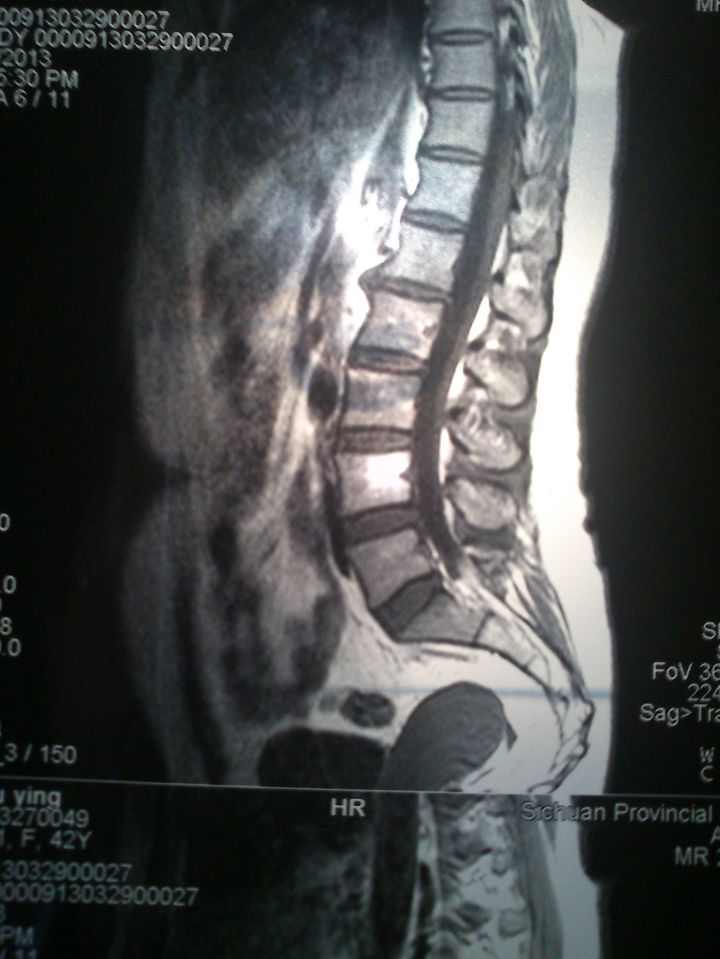

术前腰椎核磁共振显示:腰4-5椎间盘突出,神经根及硬膜囊受压.

图片尺寸1200x1600